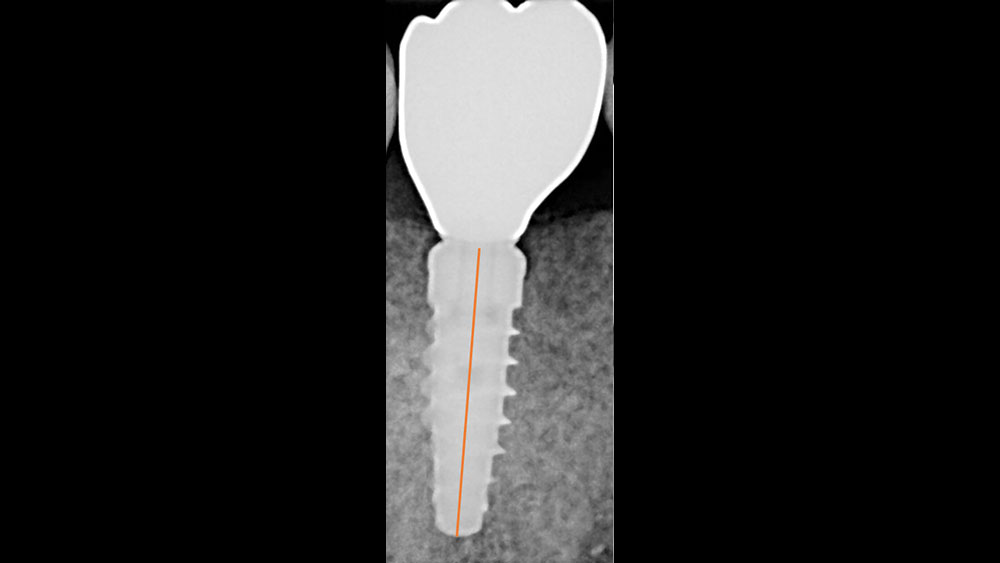

Following well-established clinical research methods, bone loss was measured as the distance from the implant shoulder to the first contact of bone to implant, from both the mesial and distal sides.

Figures 1a, 1b: Calibration of the bone loss measurements was determined by measuring the length of the implant (1a), or by measuring the diameter in cases where the implant apex was not visible (1b).